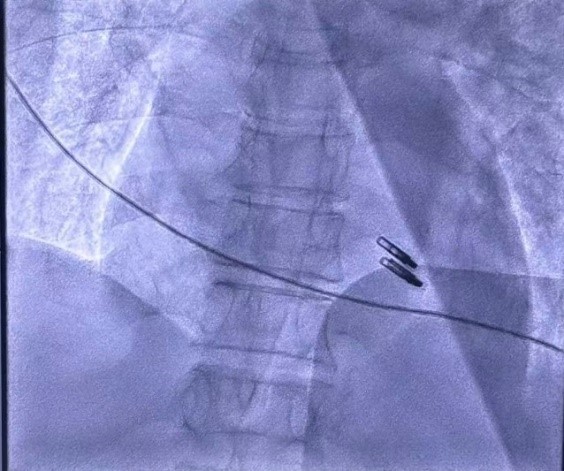

团队凭借丰富经验,拉开了一场精密手术的帷幕。在李剑平副院长的带领下,心超团队通过经食道超声在术中精准“导航”,麻醉科、胸外科、ECMO团队、ICU、血管外科等多学科专家紧密协作,金骁琦主任医师团队反复调整毫米级的介入位置,历时两小时成功完成修复!

术后复查心超显示,二尖瓣反流降至微量!手术效果立竿见影,患者心脏功能显著改善,胸闷气喘等症状显著缓解。

TEER也叫经皮二尖瓣钳夹术,是目前治疗重度二尖瓣关闭不全最成熟可靠的微创介入技术之一。经股静脉入路穿刺房间隔后,在超声引导下用特制的夹子钳夹住二尖瓣的前、后瓣叶并使之接合从而减少或消除二尖瓣返流,对团队协作、超声导航及操作精度的要求极高。此次手术的成功开展,充分彰显了我院多学科协作(MDT)的强大实力和心血管内科在微创介入领域的技术水平。